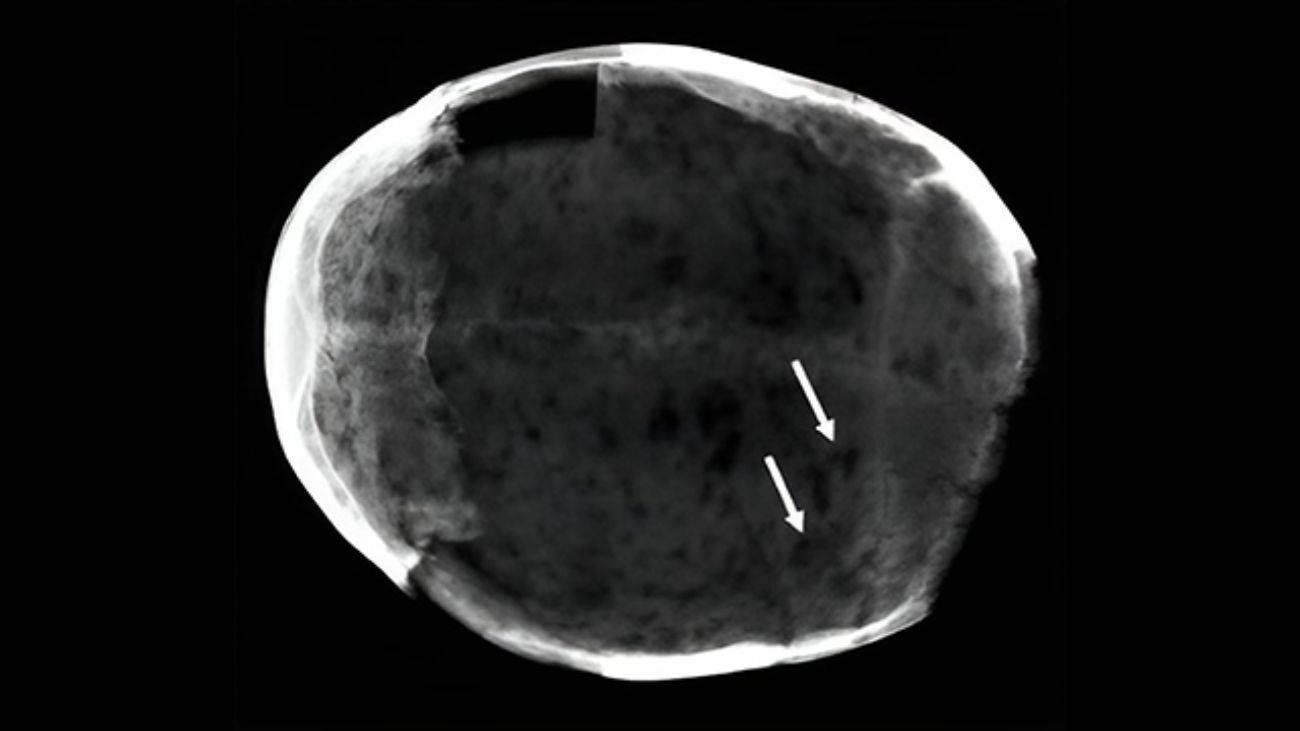

Die grafkelder herbergt een schat aan informatie: de lichamen zijn namelijk goed bewaard gebleven en zelfs deels gemummificeerd, zachte weefsel zijn daardoor nog niet helemaal vergaan. Door deze te analyseren hopen wetenschappers meer te leren over de geneeskundige praktijken uit de zeventiende eeuw.

Voor deze nieuwe studie keken ze naar gemummificeerde hersenen en troffen in twee daarvan cocaïnemoleculen aan. Ze vonden ook sporen van hygrine, een stof die alleen voorkomt in de bladeren van de cocaplant. Volgens de onderzoekers betekent dit dat de 17e-eeuwse personen de drug gebruikte in plant-vorm. Waarschijnlijk kauwden ze op de bladeren of trokken ze er thee van.